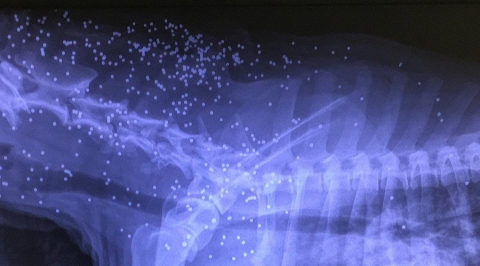

L’animale, una femmina di taglia media a cui è stato dato non a caso il nome di “Carabina”, è stato trovato ferito in strada Pezze del Sole, a Bari, il 16 gennaio scorso. «L'abbiamo portata subito nella clinica veterinaria Einaudi, che è aperta 24 ore su 24 – racconta Patrizia Giaquinto, responsabile del Canile sanitario – e quando abbiamo visto il risultato degli esami siamo rimasti allibiti».Notizia di proprietà della testata giornalistica © Barinedita (vietata la riproduzione)

Carabina è stata infatti letteralmente “impallinata” da centinaia di piombini, il che escluderebbe l’ipotesi di un errore, di un tiro partito per sbaglio. Del resto le hanno sparato anche sul muso e sulla testa, fino a renderla purtroppo cieca. Sottoposta alle dovute cure e a ben due operazioni, la cagna non è più in pericolo di vita e rimarrà per almeno due mesi sotto osservazione, perché c’è sempre il rischio di un’infezione.Notizia di proprietà della testata giornalistica © Barinedita (vietata la riproduzione)